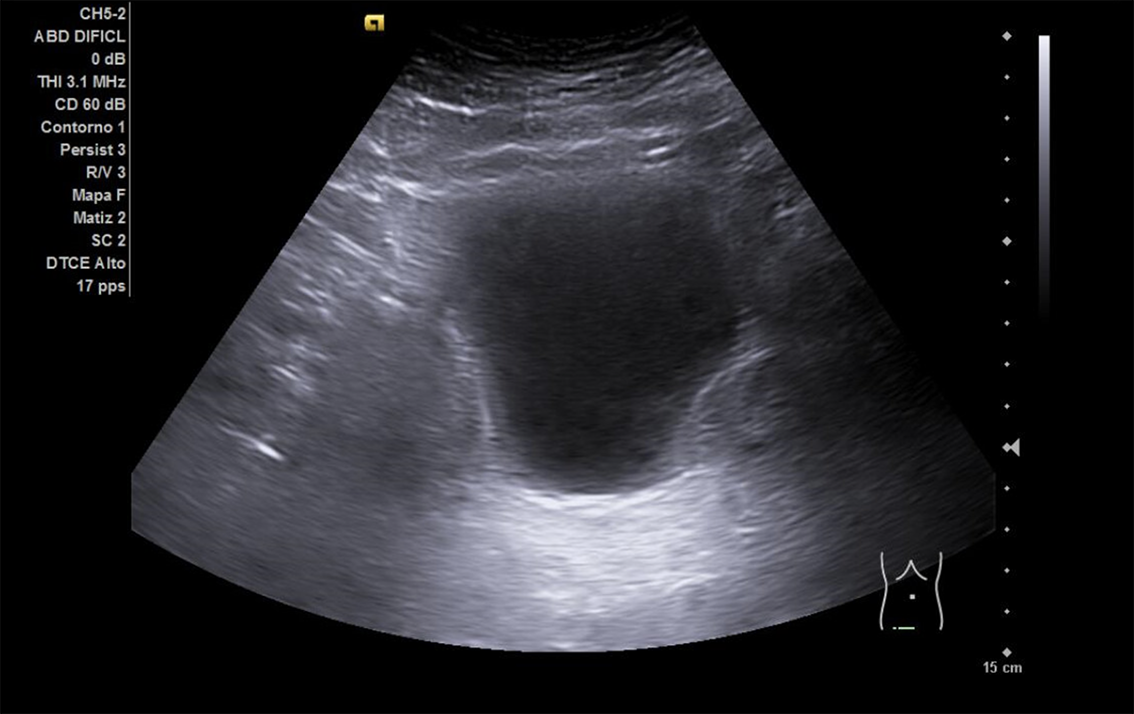

Se realiza ECO POCUS en la que se aprecia riñón derecho de morfología y tamaño normal. Riñón izquierdo con hidronefrosis grado III. A nivel de vejiga, bien replecionada se aprecia masa a nivel de pared izquierda adyacente a unión ureterovesical de 1.8 x 2,7 cm Ausencia de jet izquierdo.